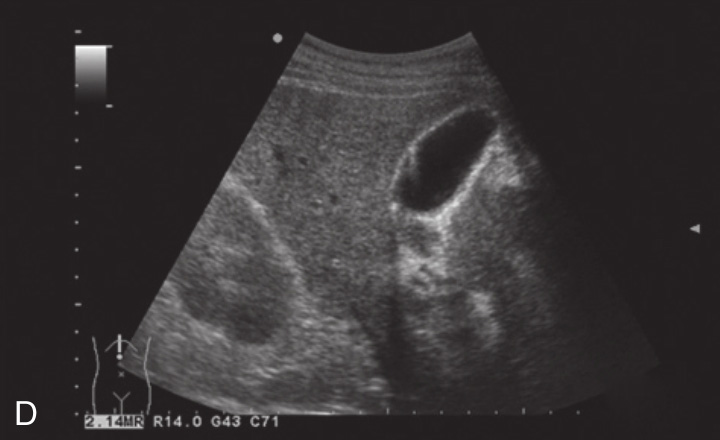

4)胆囊壁内结石:

胆囊壁多增厚,壁内可见单发或多发的微小强回声斑,后方出现多重反射回声,类似彗星尾,改变体位时结石不移动(图2-6-3D)。

图2-6-3 非典型胆囊结石灰阶超声图像

A.充满型胆囊结石;B.胆囊颈部结石;C.泥沙样胆囊结石;D.胆囊壁内结石